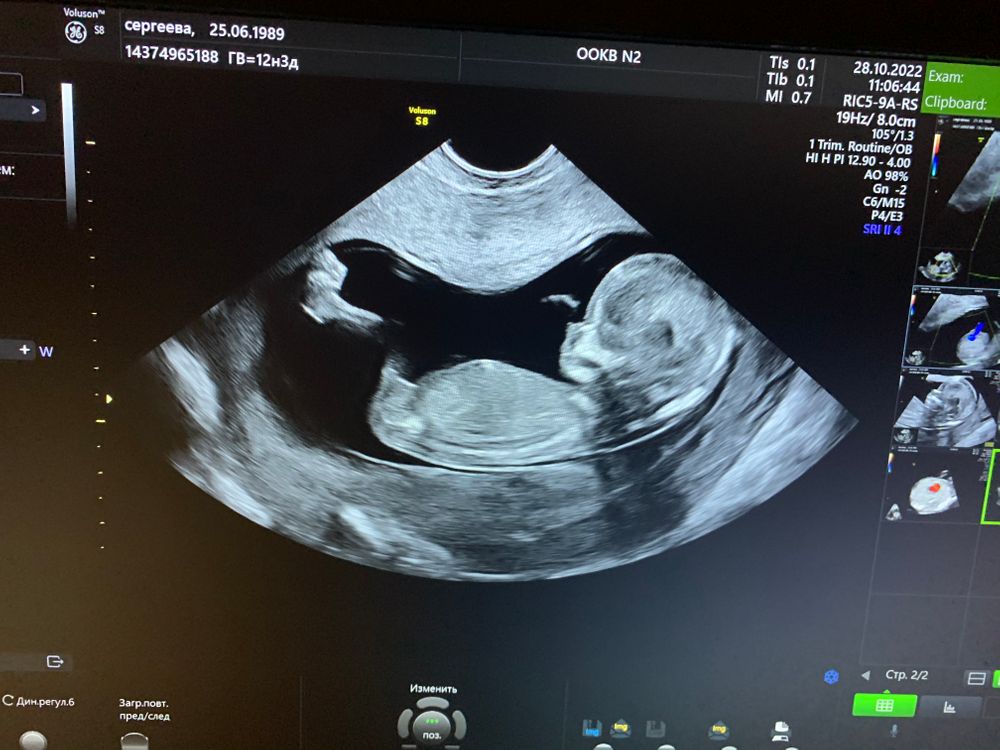

Мамы, у кого совпал пол на 1 скрининге и дальнейших? И кто в итоге родился?